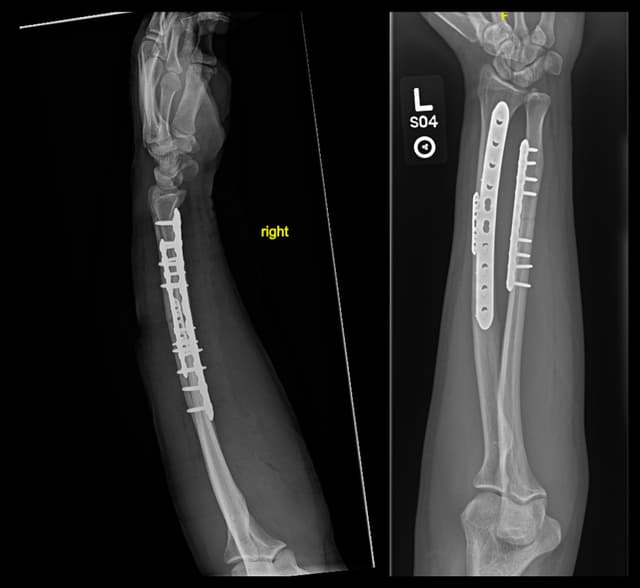

Imaging

Post-op